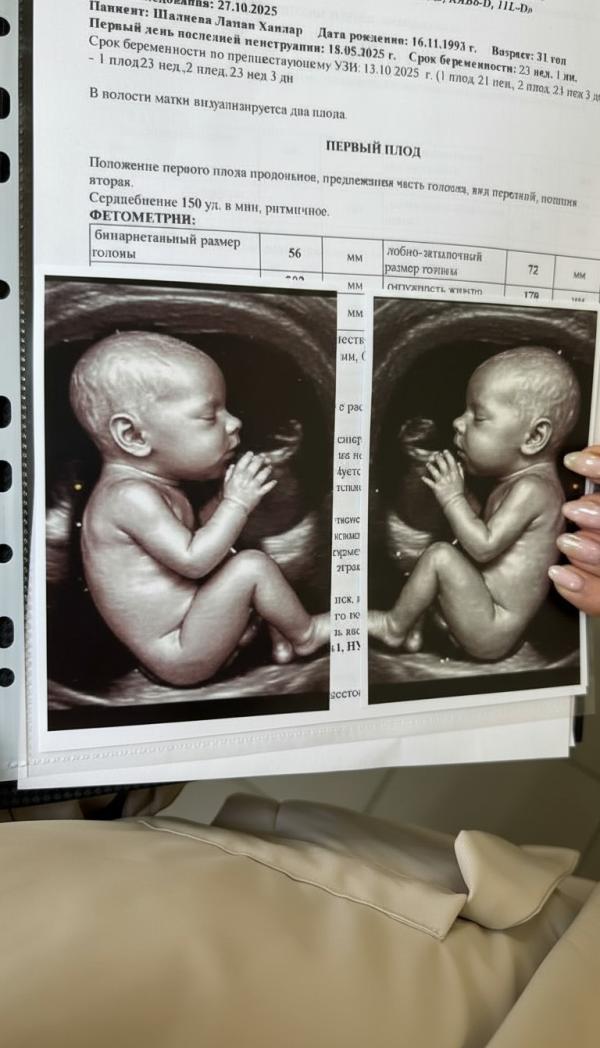

Это где такое шикарное узи ?)) или просто картинка ) отстала от жизни )

@sviridovalera, да и в 29 недель малыши не так выглядят)